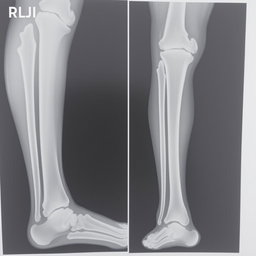

"Make medical report for leg fracture of patient, heading hospital name " national medical college hospital" hospital address: birgunj with given patient details name "Prabesh Kumar Sah" Age "18" and sex "male""